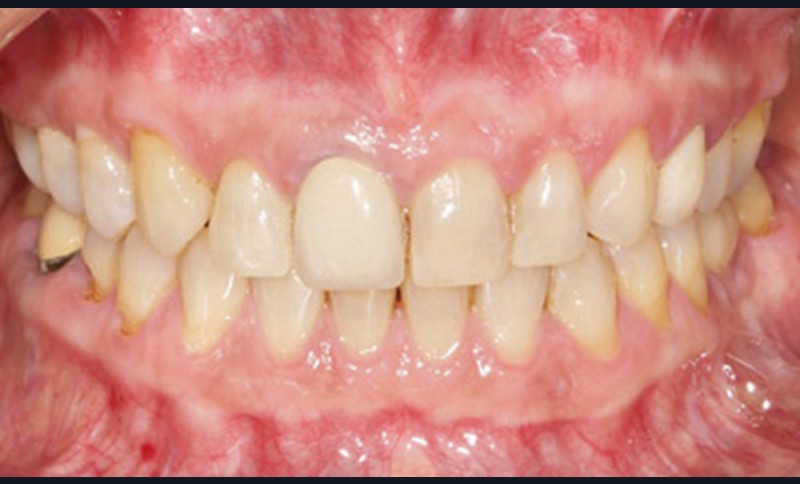

Discussion (fig. 5 à 8)

Le traitement a duré vingt-quatre mois. Les documents de fin de traitement nous montrent un sourire plus harmonieux et des rapports labiaux améliorés. De profil, la patiente a un meilleur soutien des lèvres. De plus, un léger repositionnement sagittal mandibulaire a été obtenu.

Sur la téléradiographie de profil, on note une normalisation des rapports incisifs avec un torque radiculo-palatin de l’incisive maxillaire et une vestibulo-version de l’incisive mandibulaire. La diminution de l’angle interincisif a été recherchée afin de garantir la stabilité du traitement. La superposition générale structurale révèle une rotation totale horaire qui confirme une amélioration du sens vertical.

La correction de la classe II molaire et canine a été réalisée tout en maintenant les médianes incisives centrées malgré l’implant en 36.

Il subsiste néanmoins un tip back de la 23 dû à l’effet parasite de la distalisation maxillaire.

Quant à la couronne sur la 11, il est prévu qu’elle soit refaite après éclaircissement, afin d’harmoniser sa forme et sa teinte, mais aussi la hauteur du collet avec la 21.